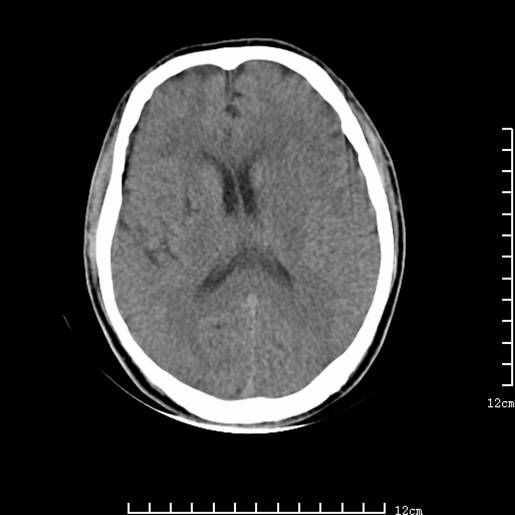

以下图像分别是3月25日凌晨及下午图像、3月27日、4月16日的ct图像。

3月25日凌晨

脑梗塞(左侧大脑中动脉分布区)。

1)左侧额颞顶叶、岛叶及基底节区(相当于左侧大脑中动脉供血区)大面积脑梗塞。2)右侧基底节区腔隙性脑梗塞。

大脑中动脉供血区大面积脑梗塞没有问题。

支持左侧大脑中动脉分布区脑梗塞。